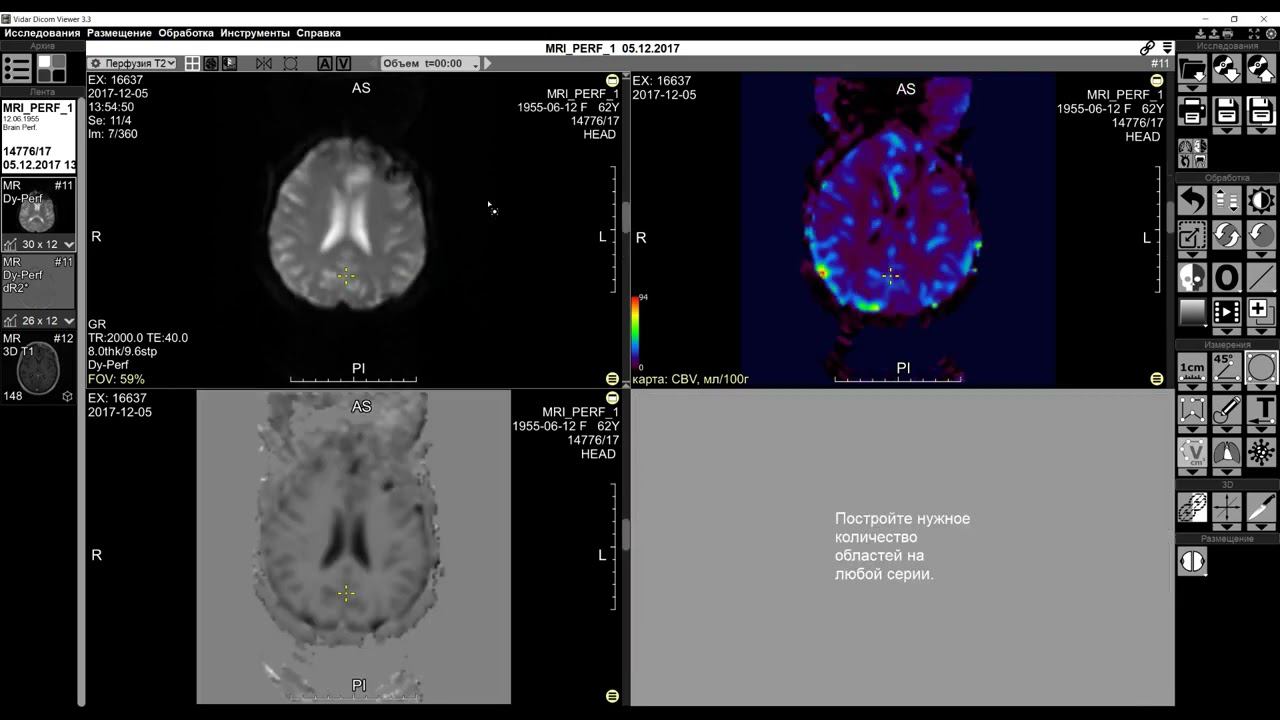

Мр перфузия

Мр перфузия 119 фотографий